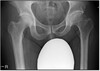

5

Perfectly